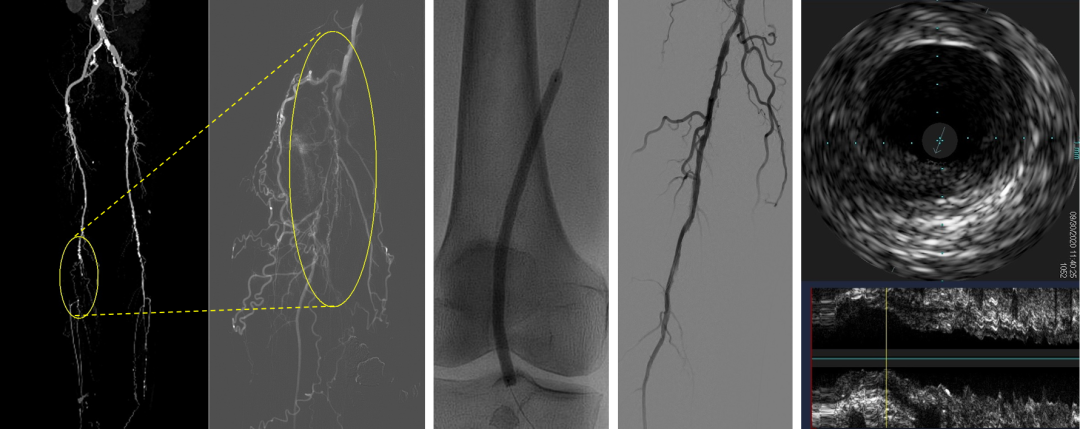

病例一:轻度钙化--刻痕球囊治疗

患者为腘动脉钙化病变,术前评估为轻度钙化。术中采用鼎科6mm×80mm刻痕球囊扩张。IVUS评估显示理想管腔获得,造影显影良好,无需补救治疗。术后常规使用DCB。